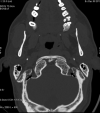

Objective The posterior condylar canals (PCCs), posterior condylar veins (PCVs), occipital foramen (OF), and occipital emissary vein (OEV) are potential anatomical landmarks for surgical approaches through the lateral foramen magnum. We performed the study to make morphometric and radiological analyses of the various emissary foramens and vein in the posterior cranial fossa. Methods Morphometric study were performed on 95 dry occipital bones and radiological analyses on computed tomography (CT) angiography images of 150 patients. The number of OFs on both sides was recorded and PCC length and mean diameters of the internal and external orifices of PCC were measured for bony specimens. Prevalence of PCV and PCV size was investigated using CT angiography. Results Mean PCC length was higher in the left side (9.85 ± 2.5). Mean diameter of the internal orifice and the external orifice diameter were almost the same. The majority of PCCs (75-79.33%) had 2 to 5 mm diameter; only 4 to 9.2% were small in size (< 2 mm). In CT angiography, PCV was not identified in 23 (15.33%) patients. PCVs were located bilaterally in 105 (70%) and unilaterally in 22 (20.5%) patients. Only 11.3% of PCVs were large in size (> 5 mm), 80% of PCVs were medium sized (2-5 mm), and 8.6% were small sized (< 2 mm). Conclusion Normal values of OF, PCC, PCV, and OEV could serve as a future reference for the understanding of the physiology of craniocervical venous drainage, which is necessary to avoid surgical complications and can also serve as a guide to surgical interventions for pathologies of the posterior cranial fossa, such as tumors and injuries.